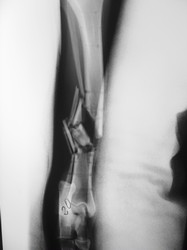

Fijación Externa

PRÁCTICAS CURSO DE FIJACIÓN EXTERNA PERFECCIONAMIENTO.

Híbrido.